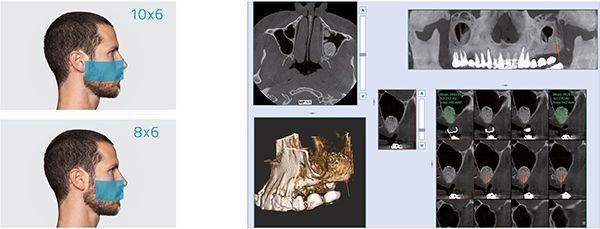

NNT. ПЕРЕДОВЫЕ ФУНКЦИИ ПРОГРАММНОГО ОБЕСПЕЧЕНИЯ

Обширные возможности передачи и обработки с оптимальной платформой визуализации.

Программное обеспечение NewTom NNT предлагает все функции, необходимые для выполнения, обработки, вывода на экран и передачи 2D и 3D результатов обследования. NNT также предоставляет различные режимы и функции приложения, специально предназначенные, чтобы планировать лучшее лечение в области имплантологии, эндодонтии, пародонтологии и рентгенографии, а также в челюстно-лицевой хирургии.

NewTom GO генерирует выдающиеся объемные изображения и для каждого FOV в диапазоне от 6х6 до 10х10 см. Выбор из 3 протоколов позволяет адаптировать требуемую дозу рентгеновского излучения к конкретным потребностям: от очень низкой для быстрого сканирования, необходимого при последующих хирургических проверках, до регулярной для планирования лечения, до очень высокого уровня детализации для анализа микроструктур.Минимальная доза, максимальное диагностическое качество

Детализированные объемы для всех клинических задач с заботой о здоровье пациентов

NewTom GO создаёт выдающиеся объемные изображения для каждого поля обзора, от 6*6 до 10*10 см. Выбор из 3 протоколов позволяет устанавливать дозу излучения, требуемую для конкретной задачи: от очень низкой для быстрого сканирования при хирургическом наблюдении, средней для планирования лечения, до очень высокого уровня детализации для анализа микроструктур.